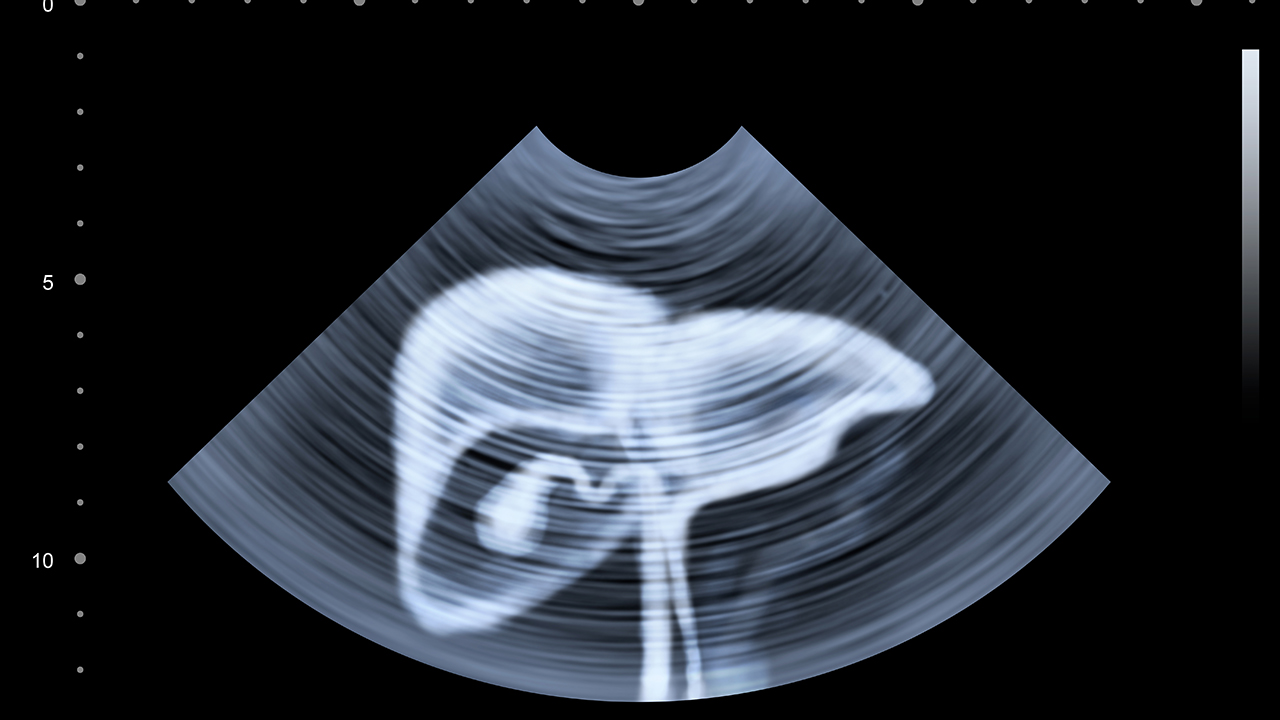

4、影像学特点:

原发性肝癌在CT或MRI上多呈"快进快出"强化特征,超声可见门静脉癌栓。继发性肝癌常表现为肝脏多发结节,增强扫描呈现与原发癌一致的强化方式,如乳腺癌转移灶呈渐进性强化。